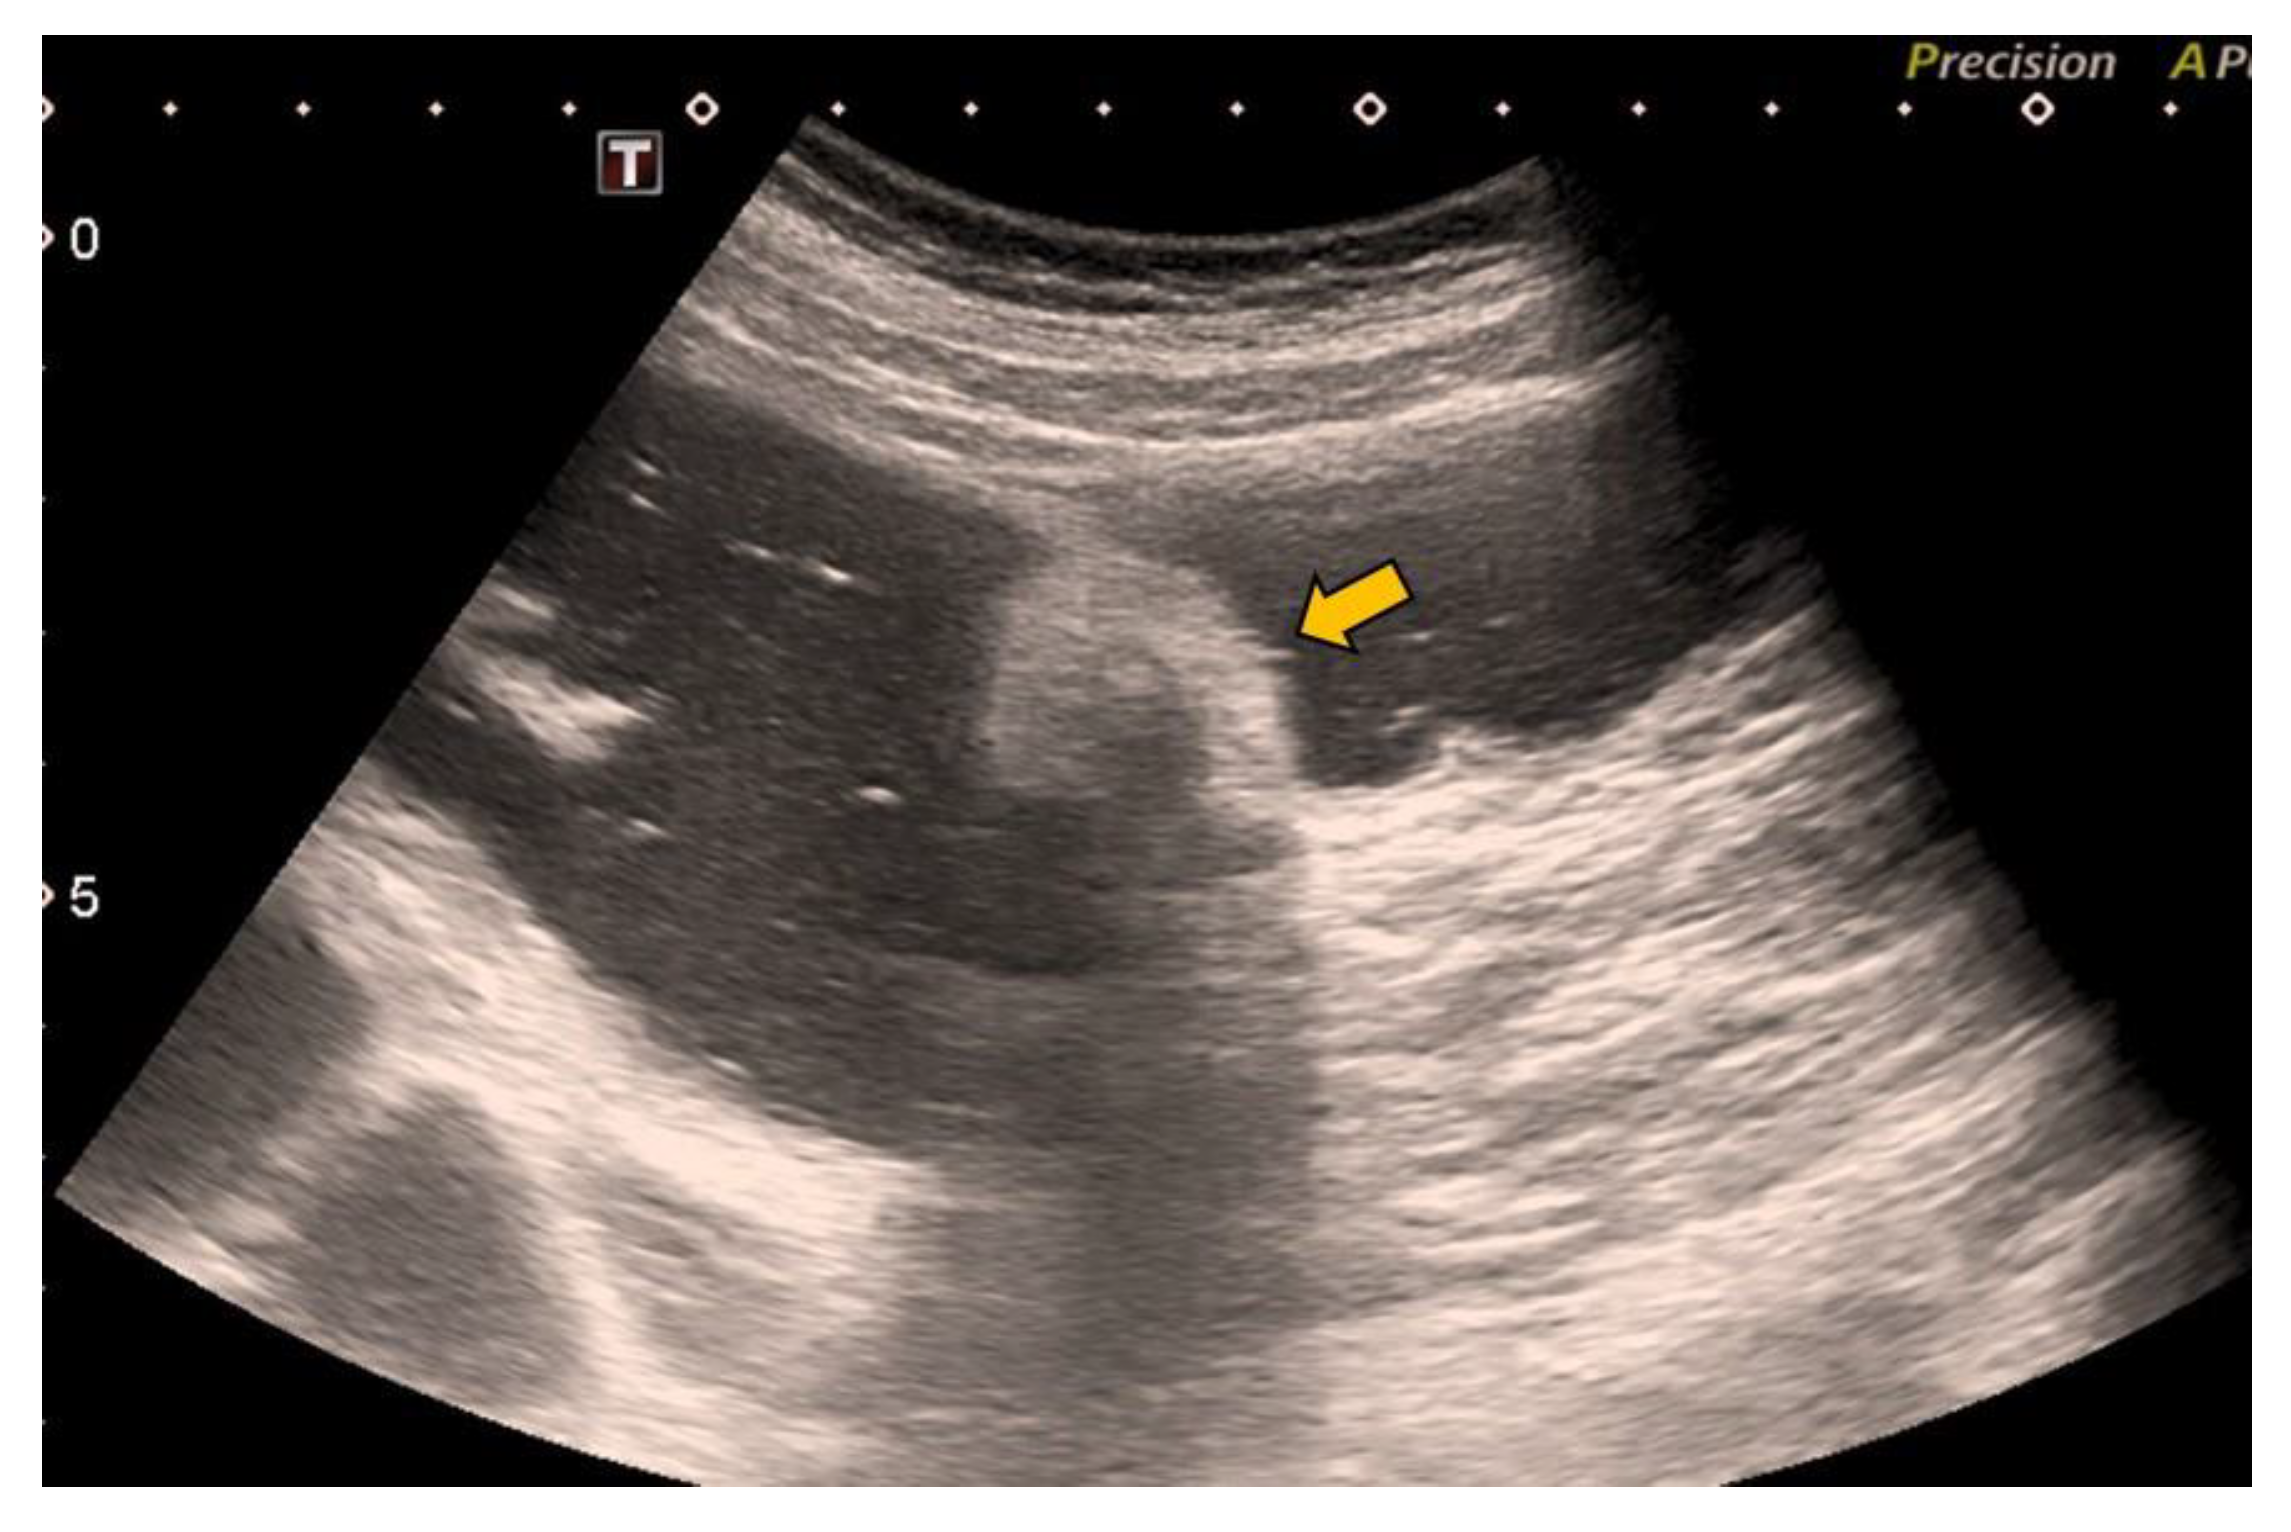

In our case, it was possible to follow up on the lipoma during biannual OCs performed because of her personal history of polyposis. Initially, it was proposed that abdominal-CT scans (Figure 1 and Figure 2) should be performed the year after each OC. This way, the size of the lesion could be monitored, and the degree of local infiltration could be determined. After the first abdominal-CT follow-up, to avoid exposure to radiation, HS (Figure 3) was included as an alternative to abdominal-CT. In the subsequent follow-up, in addition to the biannual OCs, two hydrocolonic ultrasound scans (without cleansing preparation) and one abdominal-CT scan were performed. During the seven years of follow-up, the lipoma remained stable, and the patient remains asymptomatic.

Figure 1.

Axial CT scan of the abdomen with intravenous and oral contrast showing the intracolonic lipoma in the caecum as a hypodense image (yellow arrow).

MR with fat saturation techniques can also be useful for detecting lipomas, but the detection of small lesions can be complicated [7]. The sensitivity of MR in the detection of fat composition is 100% [1]. Lipomas are easily distinguishable using abdominal-CT, as they appear as well-defined hypodense lesions between −40 and −120 Hounsfield units [36] (Figure 1 and Figure 2). The sensitivity of abdominal-CT in the detection of lipomas is 58–100%, and they have a characteristic image that looks like a “target sign” or “doughnut sign” [5,37]. Abdominal-CT is a very useful technique in urgent cases, but for follow-up, it presents problems due to the associated radiation. In addition, local infiltration can be difficult to exclude using abdominal-CT or MR [1].